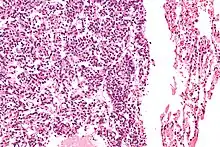

| Micrograph of a typical pulmonary carcinoid tumour. | |

Typical pulmonary carcinoid tumour is a subtype of pulmonary carcinoid tumour. It is an uncommon low-grade malignant lung mass that is most often in the central airways of the lung.[1]

The definitive diagnosis is rendered by a microscopic examination, after excision. Typical carcinoids have cells with stippled chromatin and a moderate quantity of cytoplasm. They typically have few mitoses and lack necrosis. By definition, they are greater than 4 mm in largest dimension; smaller lesions are referred to as pulmonary carcinoid tumourlets.